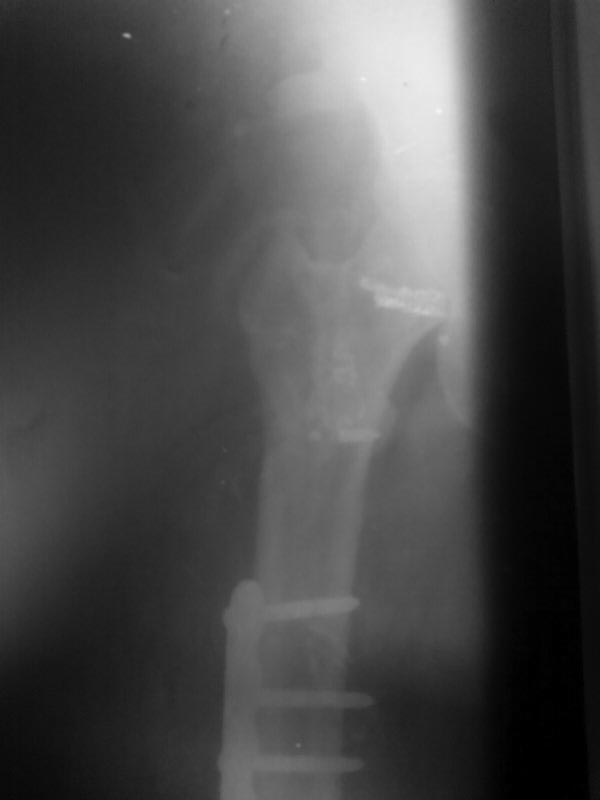

Вариант реконструктивного стержня с латеральной точкой введения также

рассматривается.

Так выглядит проксимальный отдел бедра на данный момент.